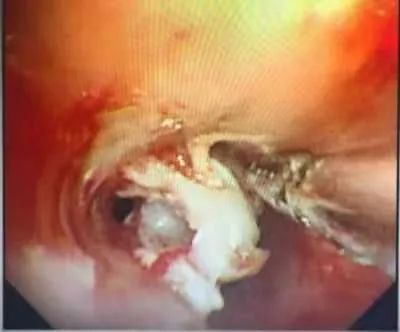

气管镜再次进入,果然,在左总支气管内,还有一整块虾肉卡在里面。于是,再次准备用异物钳夹取,但是虾肉质地滑软,无法顺利夹出。

该怎么办?这时严主任说道:我们可以先用冷冻法,使虾肉硬化,然后再用异物钳取出。于是经多次冷冻后,硬化的虾肉终于取出。整个操作过程,耗时38分钟。

(镜头下的虾肉和取出后的虾)